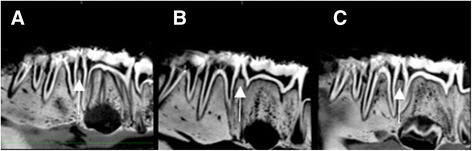

CBCT images were saved in DICOM standard format (version 3.0) and were imported to an open-source DICOM viewer (OsiriX 5.6, Pixmeo, Geneva, Switzerland), installed in an independent workstation (MacOS X v.10.6.8, Apple Inc., Cupertino, CA, United States). Analysis was performed independently and on separate occasions using an imaging post-processing protocol (OsiriX tool 3D-MPR, Pixmeo, Geneva, Switzerland). The images were analyzed simultaneously in axial, coronal, sagittal, parasagittal and circumferential views. Examiners were free to adjust brightness and contrast and to zoom in/out images, but not to apply filters. Figure 3a shows a sagittal section of control between PM2 and M1, 3B presents a two-hour lesion between PM2 and M1 and 3C shows a four-hour lesion between PM2 and M1. Figure 4a depicts a crater formed after 6-hour acid exposure between PM2 and M1 and 4B illustrates a vertical defect formed after 6 h of acid exposure between PM1 and PM2. Conventional intraoral radiographs were observed directly in a negatoscope inside a dark room. Examiners were free to use magnifying glasses. Figure 5a illustrates 6-hour lesion between M1 and PM2 and a control site between PM1 and PM2. Figure 5b shows four-hour lesion between PM1 and PM2 and two-hour lesion between PM2 and M1. There was no time limit for viewing radiographs or CBCT images.

Fig. 3.

Sagittal sections of CBCT images. a. No lesion (control) between second premolar and first molar. b. Two-hour lesion between second premolar and first molar. c. Four-hour lesion between second premolar and first molar

Fig. 4.

Sagittal sections of CBCT images. a. Crater formed after 6 h of acid exposure between second premolar and first molar. b. Vertical defect formed after 6 h of acid exposure between first and second premolar